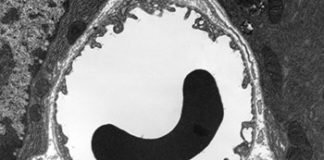

Ustanovljeno je da 97,3 posto ljudi koji su imali bolest gušterače zapravo imaju dijabetes tipa 3c.Znanstvenici sa Sveučilišta Surrey proučavali su medicinske podatke dva...